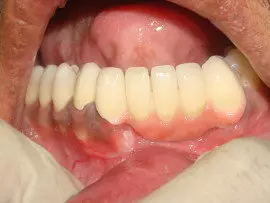

Soft tissue grafts are basically tissue obtained from palatal region under local aneasthesia to cover isolated & also long areas of gingival recessions.

Artificial readily available soft tissue membrane like collagen, alloderm, PLA PGA & Vicryl  can be also used to correct gingival recession.

More Recent & newer advanced techniques include use of growth factors & patient own blood factors like platelet derived growth factors, concentrated growth factors, platelet rich plasma, platelet rich fibrin.

CGF is a substance of patient’s own blood enriched with plasma and platelets & contains various Concentrated Growth Factors [CGF]. These help in reduced bleeding, enhanced & faster healing, decreased inflammation & swelling and accelerated bone & also soft tissue formation.